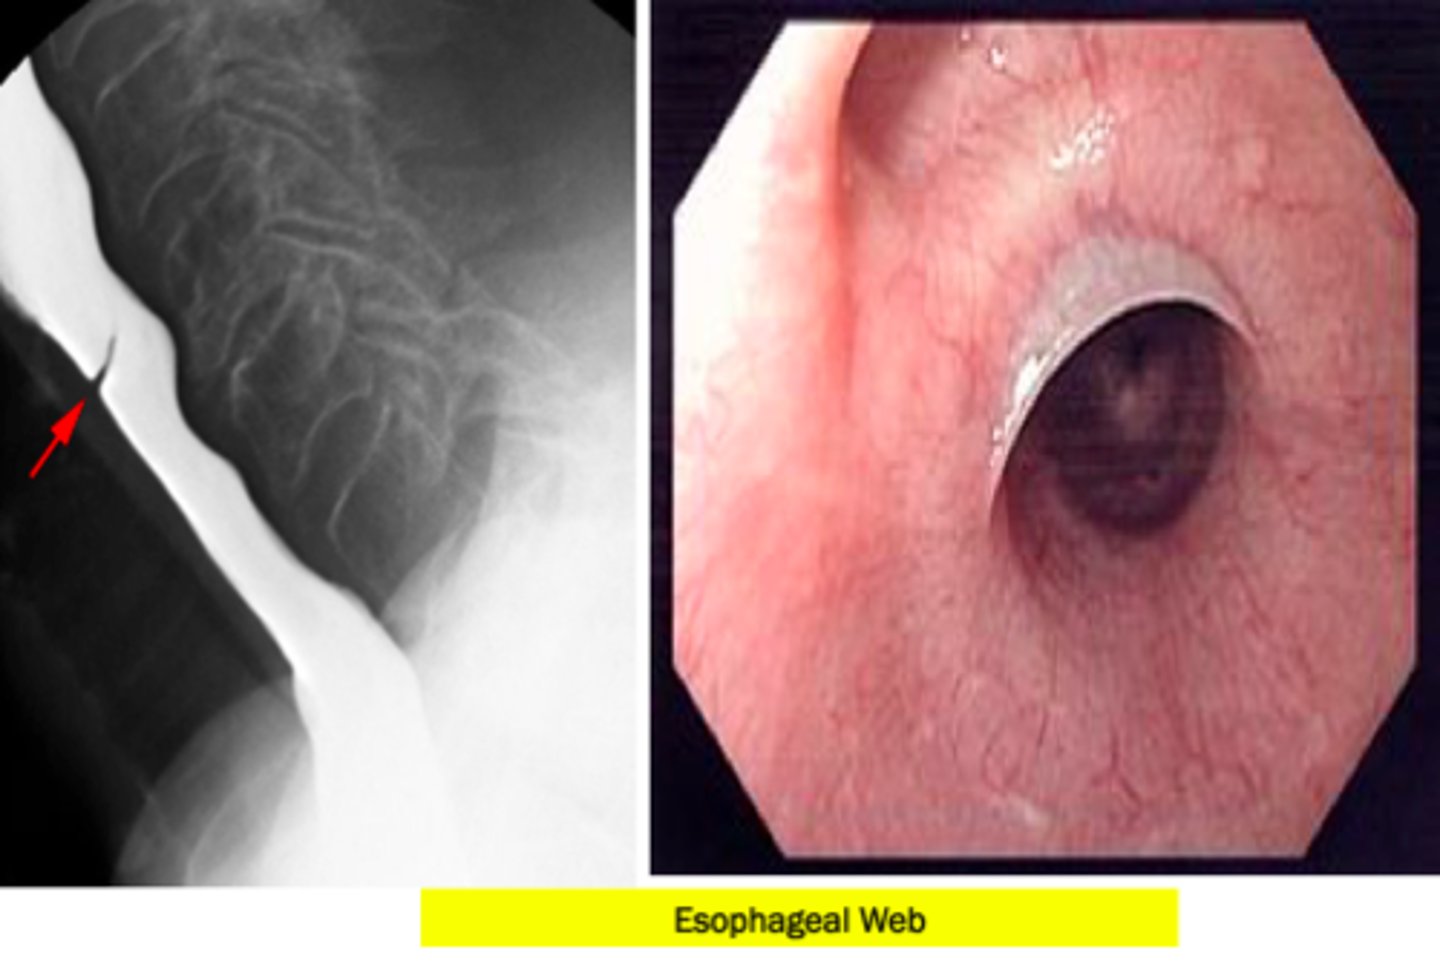

Your patient has iron deficiency anemia and complains of GERD-like symptoms and has difficulty swallowing. You perform a barium swallow and EGD. What is the treatment for this patient?

Esophageal dilation or electrosurgical incision and long term PPI therapy.

This patient has esophageal webs